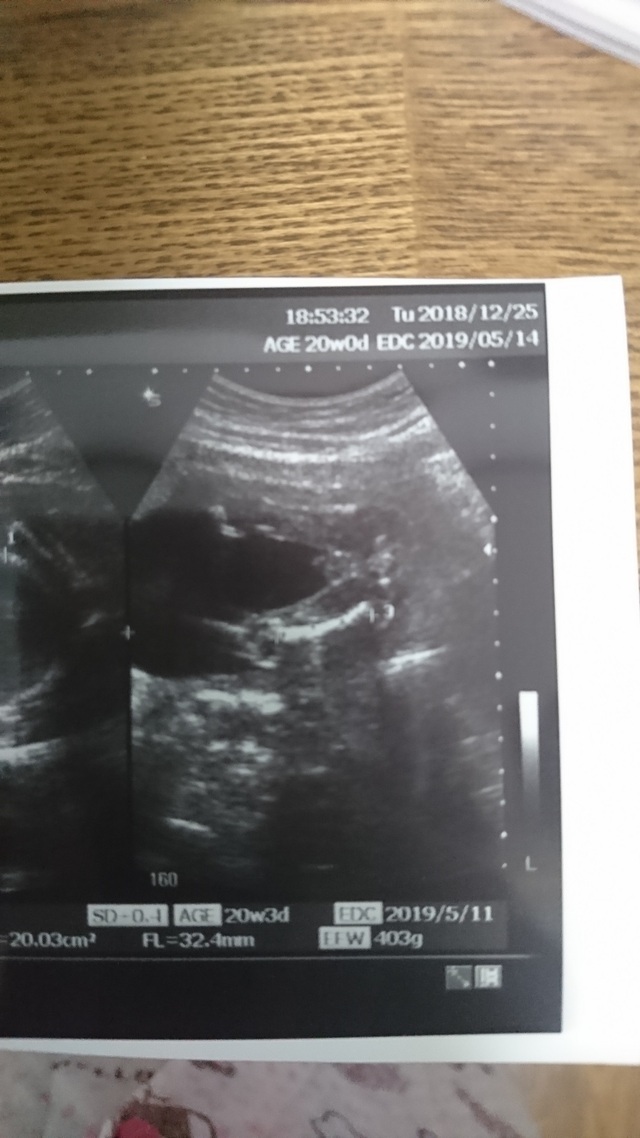

22週0日(22w0d・女の子)|ao:-) さん(29歳)

エコー写真撮影時のエピソード:

なかなか性別が分からない我が子。

この日もお股を見せてくれず。

すこーし、週数より小さめに育っている我が子ですが、私自身も小さめに生まれたのでそんなに不安は感じませんでした。

つわりも少なく、安定期に入って主人と一泊旅行に行ってきた次の日の健診だったので体重増加を先生に注意されたのは今となっては良い思い出です。